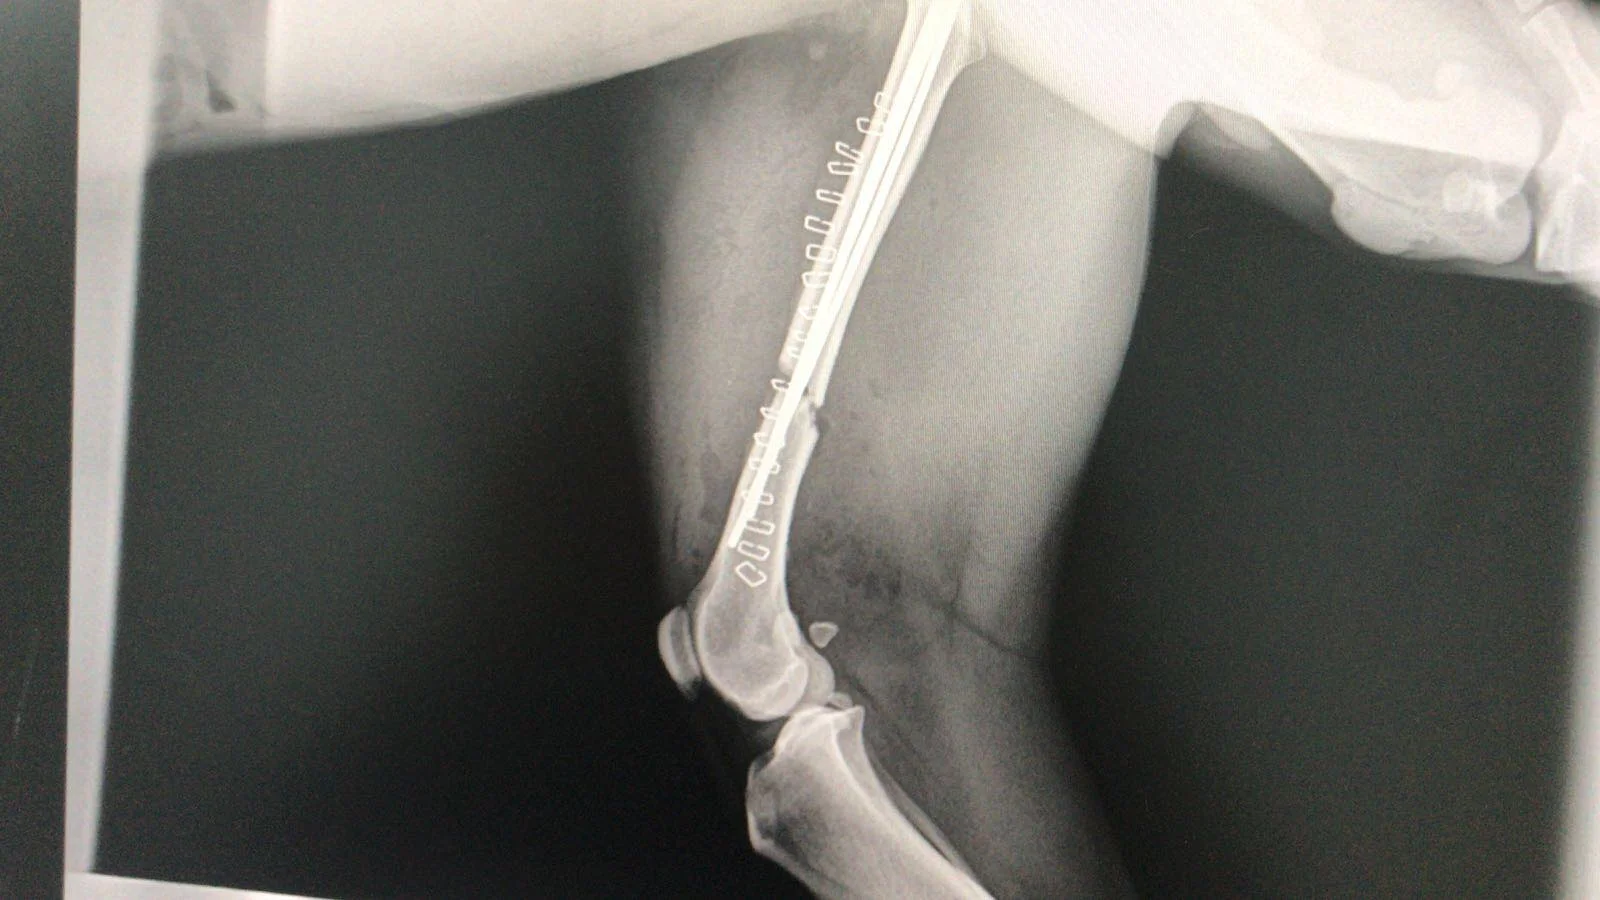

Post surgery, break now pinned